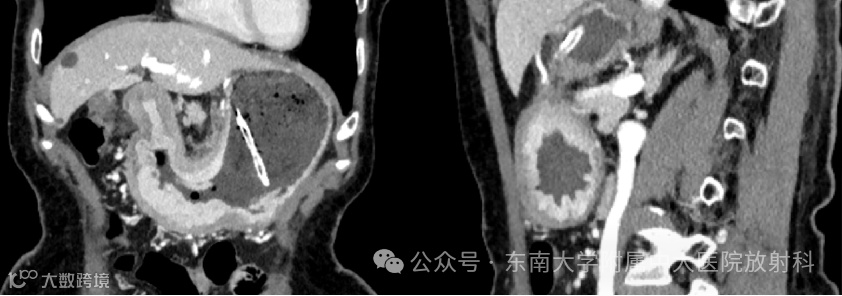

病例2

男,59岁 -

主诉:上腹腹痛腹胀7月 -

现病史:患者7月前进食后出现上腹腹痛腹胀,烧灼样刺痛,进食较快及进食多后,疼痛明显,未予重视。患者6月前腹痛明显,于当地医院就诊,予以“雷贝拉唑、铝镁片”等治疗,具体不详,服药后腹痛缓解。3个月前患者再次出现上腹腹痛,烧灼样刺痛,阵发性疼痛,进食后及夜间疼痛明显,自行口服“护胃”药物后无明显缓解,有恶心呕吐感,未吐,无畏寒发热,无胸闷胸痛,无呼吸困难等不适。于1月前于当地医院查胃镜提示:食管粘膜静脉瘤,食管粘膜下隆起性质待定,胃体溃疡浸润型Ca,慢性萎缩性胃炎C1,十二指肠降部粘膜隆起,活检病理提示:低分化腺癌。现患者为求进一步诊治,门诊以“胃恶性肿瘤”收治入院。病程中,患者一般情况可,食纳睡眠可,小便正常,大便颜色正常,约3天1次。近期体重减轻约1.5kg

影像学检查